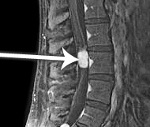

• МРТ спинного мозга. МРТ-миелография служит «золотым» стандартом диагностики подкладки. Дополнительный контраст позволяет детально изучить компоненты образования (кисты, кровоизлияния), чтобы отличить раковые ткани от отека брюшины. Если магнитно-резонансная томография не может быть выполнена, выполняется компьютерная томография позвоночника.